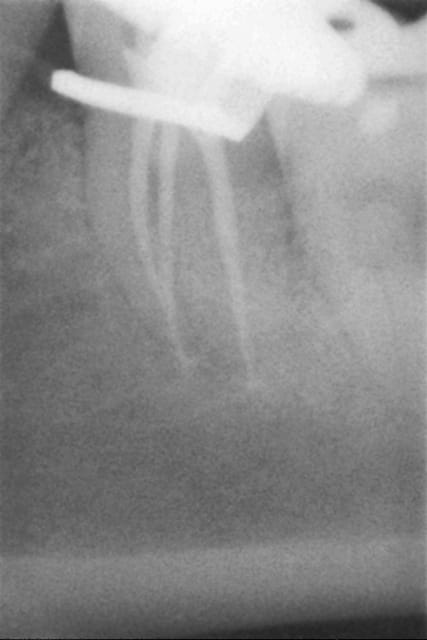

J'ai réalisé une endo sur la 36 début 2015 afin de réaliser un tfm et une coiffe ccm.

une félure sur les racines mésiales ? as tu fais de la condensation latérale ?

non pas de condensation latérale, aujourd'hui je n'ai pas fait de lambeau mais un curetage soigneux sous AL, je dois la revoir dans 15 jours à 3 semaines pour voir ce que ça donne mais bon je ne le sens pas très bien tout ça!!!

Je veux pas dire mais le dépassement en mésial a pourvu l'os en germe et on a une infection qui remontre depuis l'apex vers le haut, après un autre élément se surajoute, à voir du côté de ce qui a été écrit plus haut.